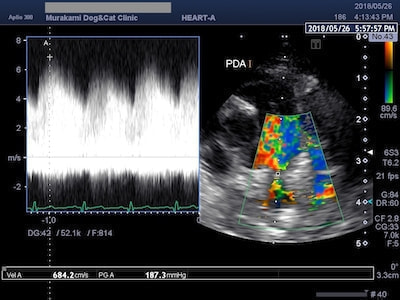

動脈管開存症(PDA)

動脈管開存症(PDA)は、犬の先天性心疾患の中で最も多くみられる疾患です。胎生期の動脈管は生後まもなく自然閉鎖しますが、うまく閉鎖できずに遺残してしまった結果、 動脈管を介して大動脈から肺動脈へ短絡血流が流れ込みます。治療には外科的に動脈管を閉鎖する必要があり、開胸手術による動脈管結紮術やカテーテルによるコイル塞栓術が適応となります。

肺高血圧症を合併したPDA

PDAを放置すると、肺血流量の増加に伴う左心容量負荷や肺高血圧を招きますので、なるべく早期に動脈管を閉鎖する必要があります。肺高血圧症が進行し肺動脈圧が高くなりすぎると、動脈管の閉鎖には時期が遅すぎるため手術不適応となってしまいます。一般にPDAの約半数は1年以内に亡くなってしまうため、様子を見過ぎず早めにご相談ください。